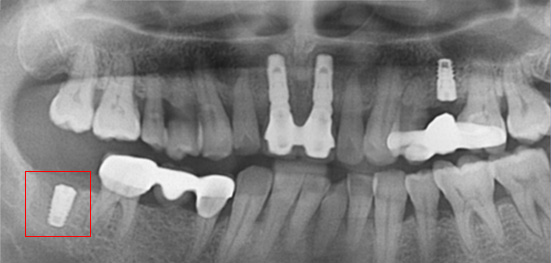

아래턱 어금니 발치 후 장시간 방치하여 잇몸 뼈 소실이 심한 상태로 내원. 뼈 이식 후 임프란트를 식립하였습니다.

잇몸 뼈 소실이 심한 상태로 내원

뼈 이식 후 치조골 밀도가 높아진 모습

잇몸 뼈가 녹아내려 임플란트 12개 진단을 받고 내원한 환자, 고운미소에서 치주치료를 시행한 결과 전치부 잇몸이 개선되어 발치 하지 않고

크라운으로 수복하였고, 어금니는 상악동거상술 후 6개의 임플란트를 식립하였습니다.

잇몸 염증으로 치조골 손실이 많은 상태

잇몸 건강이 회복된 앞니는 크라운으로 수복